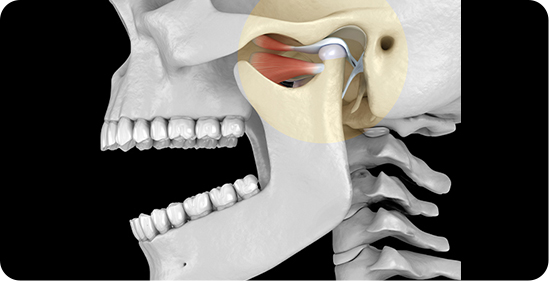

Temporomandibular Joint (TMJ) Procedures

The normal function of the temporomandibular joint (jaw joint) can be affected by various conditions, leading to clinical symptoms such as painful or restricted mouth opening, clicking sounds, or habitual dislocation of the joint. At Kamala Dental, these disorders are accurately diagnosed using advanced diagnostic aids and managed through conservative or surgical methods. In severe cases such as ankylosis, surgery becomes essential, involving the removal of fused segments and reconstruction of the joint to restore function.